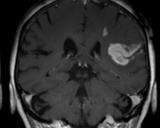

Исследователи из Калифорнийского университета в Дэвисе предложили усовершенствование для магнитно-резонансной томографии (МРТ), которое позволит обнаруживать даже очень маленькие опухоли. Работа была опубликована в журнале Nature Nanotechnology...

27.05.2020